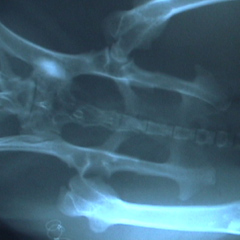

右の股関節が脱臼している。

時間がたっている場合は麻酔下で整復しても再脱臼する場合が多く、うまくいかないことが多い。

この状態では上に上がった大腿骨頭(丸い部分)が股関節側の骨に当たり痛みが出る。骨も正常な位置になく上に上がっている。 |

大腿骨頭切除術を施したうさぎ

骨は正常な位置にあり周りの太い筋肉によって、足はしっかり支えられる。通常1週間で足を使えるようになる。 |